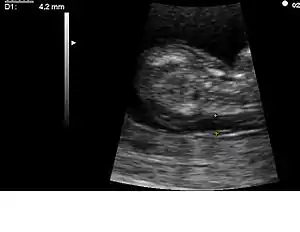

Medición del pliegue nucal mediante ecografía convencional.

A partir de 1979 se dispone en los laboratorios de una prueba en sangre que permite establecer una sospecha diagnóstica para varios defectos congénitos (espina bífida y otros defectos del tubo neural). Esta prueba es la determinación de los valores de AFP (alfa-fetoproteína), que se encuentran aumentados en los embriones que presentan estos trastornos del desarrollo. Varios años después se establece una relación estadística entre valores bajos de esta proteína y la aparición de trastornos cromosómicos, en especial del SD. En años posteriores se descubrieron algunas asociaciones similares con otras sustancias en sangre materna. Hoy día es común la determinación de AFP, estriol y hCG (Gonadotropina coriónica humana) para determinar el riesgo de aparición del SD. A esto se le llama «triple prueba». Algunos laboratorios incluyen la determinación de inhibina (cuádruple prueba). Los valores de estas sustancias en sangre, así como datos acerca de la edad materna y los antecedentes personales y familiares permiten calcular un riesgo de aparición de SD, pero no suponen un diagnóstico de certeza. Determinadas mediciones que se realizan durante las ecografías (longitud del fémur, grosor del pliegue nucal, y otras) también aportan información para el cálculo de ese riesgo, pero tampoco permiten establecer el diagnóstico definitivo.